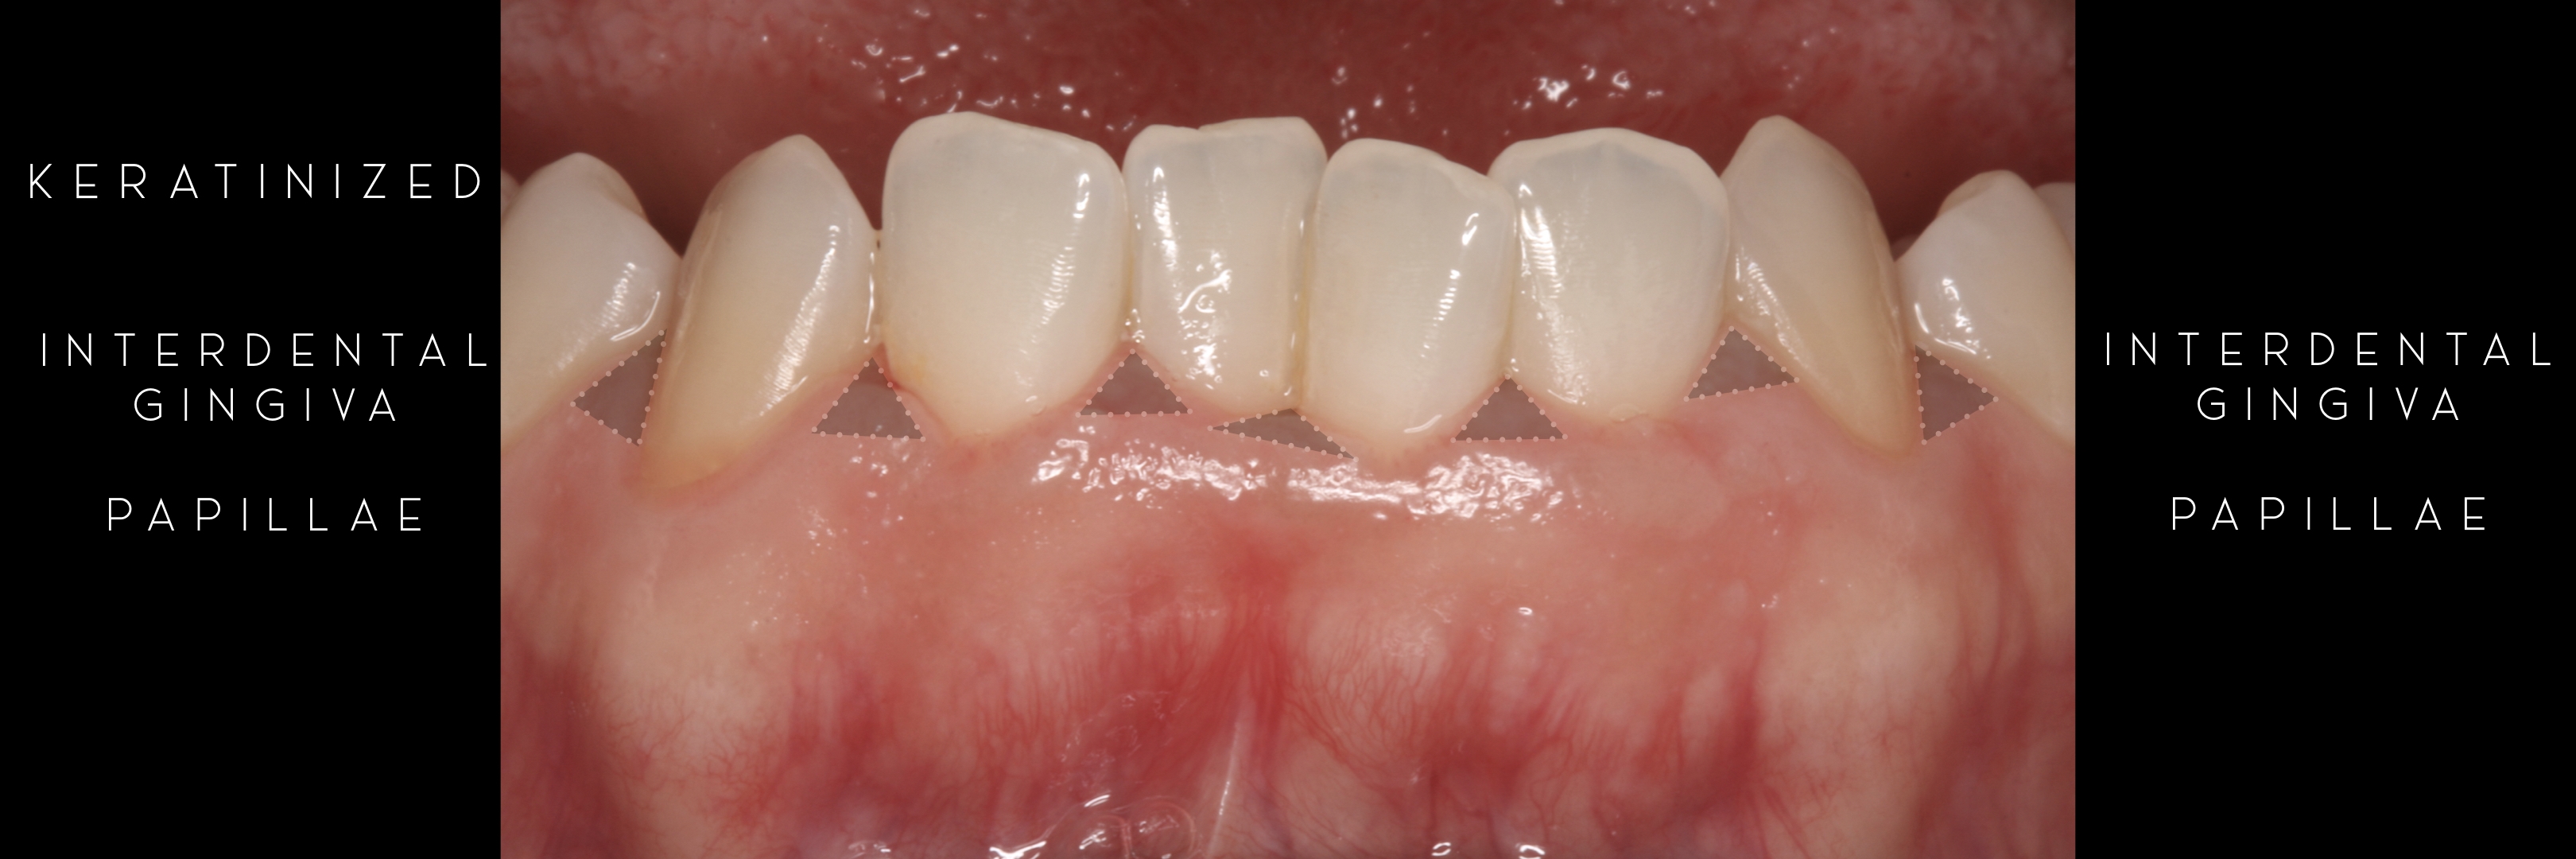

Interdental Gingiva

Keratinized Gingiva

KERATINIZED gingiva includes

the free gingiva

(marginal gingiva & papillae)

and the attached gingiva extending from the gingival mar­gin to the mucogingival junction.

Generally we tend to forget about these 2 parameters, free and the attached gingiva are both essential parts of the keratinized gingiva.